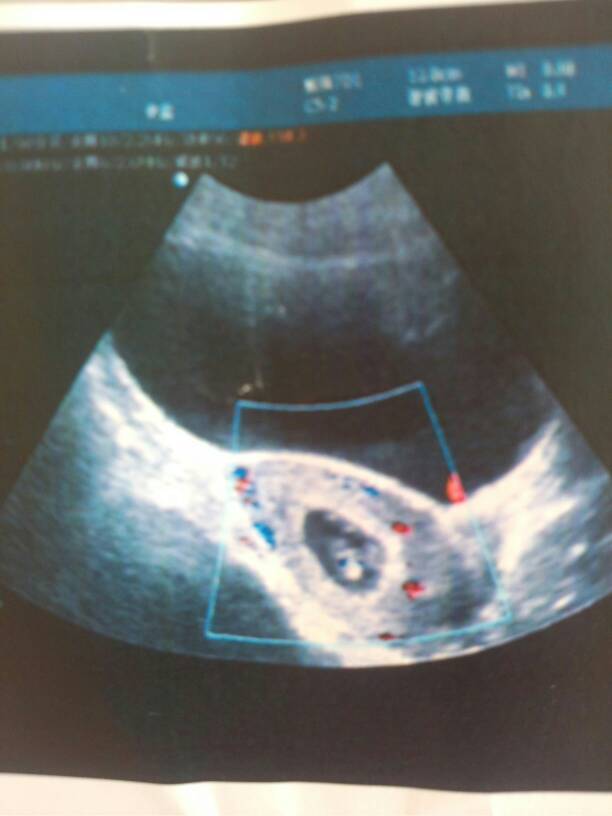

昨天刚做的b超检查帮我看一下为什么有那么多的红点啊 昨天刚做的b超检查帮我看一下为什么有那么多的红点啊 点击展开 159*****309 2014-06-21 08:35 为您推荐: 其他回答 你好,彩超这个状态是在测血流信号,身体内正常器官组织都会有血流在流动的,红的是动脉血,蓝的是静脉血,这是正常的,不用担心。 另外从宝宝的图像看,应该两月左右或两个多月了,这个时间应该有心管搏动了,只要有,就是正常的。 明年花好 2014-06-21 10:49 相关问题 为什么昨天医检查做了B超,今天肚子痛 昨天有咖啡色分泌物,偶尔有一阵儿肚子痛,医生非得让我做B超检查是否宫内孕才看是否保胎,41天做B超